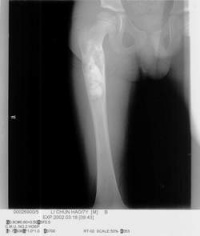

一X线:

X线平片位于长骨干骺端,呈圆形、卵圆形或柱形,沿长骨纵轴发展,表现为轻度膨胀性生长,局部骨皮质变薄,边缘光整,无骨膜增生。合并病理骨折时,骨碎片向囊内移位,称“碎片陷落征”,有助于鉴别。